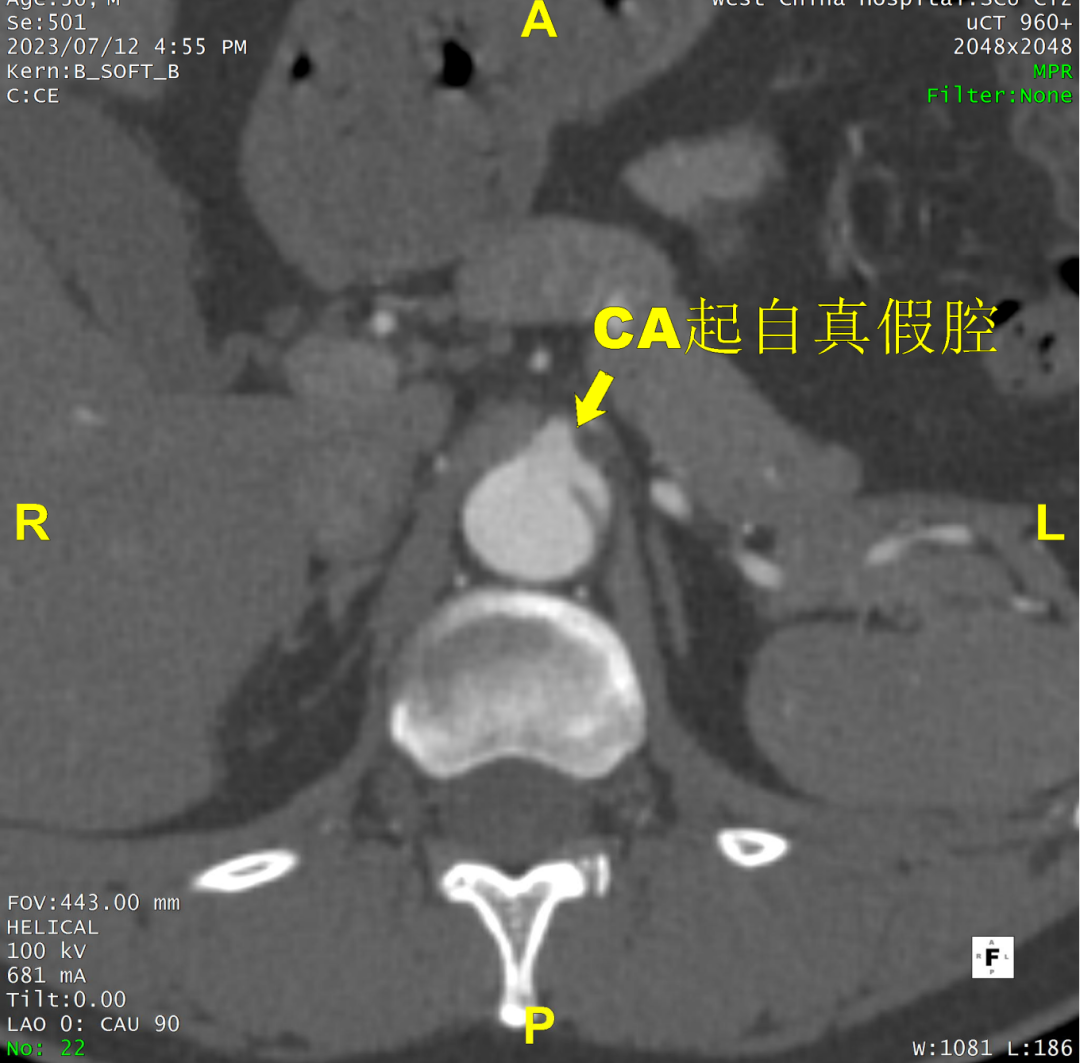

术前CTA评估与测量

术前CTA提示主动脉夹层(Stanford B型,Debake llI型),主动脉弓及降主动脉瘤样扩张,累及左锁骨下动脉起始段,管径最粗约7.4cm,夹层初破口位于降主动脉起始段,向下累及至腹主动脉(约平胸12椎体水平),真腔小,假腔大,腹腔干发自混合腔,肠系膜上动脉、下动脉,双肾动脉均起自真腔,双肾灌注未见差异。